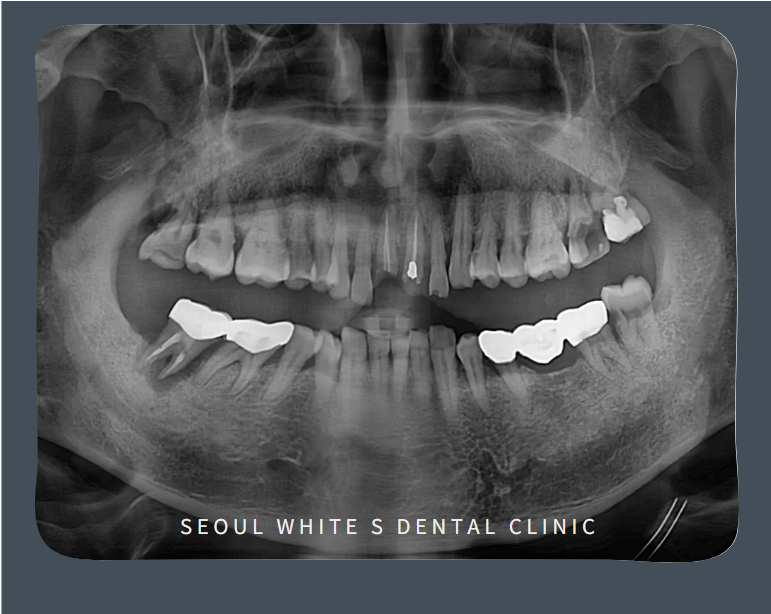

처음 내원하셨을 때, 모습입니다. 눈에 띄는 부러진 앞니 문제뿐만 아니라 양측 위아래 어금니들도 우식과 치주 질환이 상당히 진행된 상태였습니다.

영도치과, 서울화이트S치과는 살리기 어려운 앞니는 발치 후 임플란트를 식립하여 심미적인 기능을 회복하고, 기능을 하지 못하는 어금니는 발치하는 것으로 치료 계획을 세워드렸습니다.